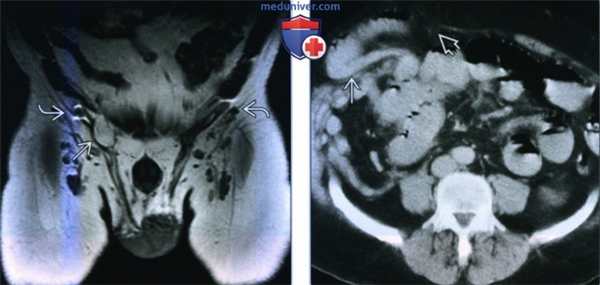

(Слева) МРТ T1ВИ, коронарный срез: определяется небольшая жиросодержащая прямая паховая грыжа. Артефакт магнитной восприимчивости возле глубокого пахового кольца с двух сторон обусловлен материалом сетки наложенной при герниорафии.

(Справа) КТ без контрастирования, аксиальный срез: определяется грыжа спигелиевой линии. Тонкий кишечник выпячивает через промежуток в стенке живота прямо латеральнее атрофированной прямой мышцы живота. Грыжи спигелиевой линии в большинстве случаев возникают ниже дугообразной линии, поскольку у прямой мышцы живота отсутствует задняя оболочка.